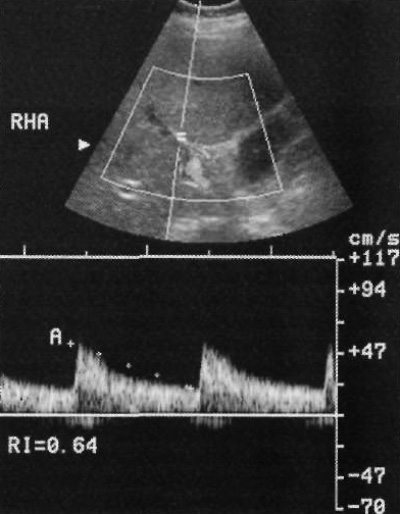

В норме печеночные артерии демонстрируют пульсовые волны низкого сопротивления. Индекс сопротивления ≥ 0,5 (как правило, 0,6-0,7). Увеличенные значения индекса сопротивления (0,7-1,0) в норме определяются после приема пищи, что обусловлено оттоком крови из печени в мезентериальное русло. Увеличение сопротивления можно наблюдать сразу после трансплантации печени, что ни коим образом не коррелирует с риском отторжения (см статью «УЗИ трансплантата печени»).

Низкое сопротивление (< 0,5) свидетельствует о шунтировании кровотока, тромбозе печеночной артерии или ее стенозе. Печеночный артериальный кровоток может повышаться при циррозе печени и некоторых опухолях (фото 1).

Фото 1. Спектральная допплерография печеночной артерии в норме. Индекс сопротивления – 0,64